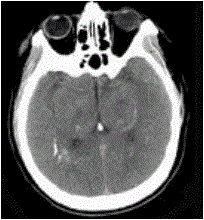

问题 男,52岁,无明显不适,CT检查如图所示,最可能的诊断为()

选项 A.脑血管畸形 B.结节性硬化 C.甲状旁腺低功能下 D.脑颜面血管瘤 E.转移瘤

答案 C